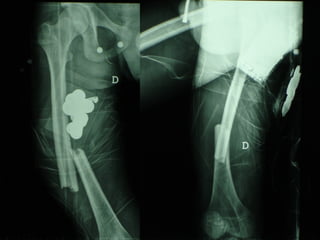

Un’altra situazione di emergenza ortopedica è rappresentata dalle fratture delle ossa lunghe in pazienti con gravi traumi cranici e toracici

INDICAZIONI COMUNI Fratture sovracondiloidee Fratture intercondiliodee Fratture diafisarie distali PARTICOLARI Fratture con grave osteoporosi Fratture periprotesiche

VANTAGGI CHIRURGIA MININVASIVA Mini Open Inserimento della placca sottocutaneo per scivolamento Viti percutanee Preservazione dei tessuti molli Ridotto danno vascolare Rapida ripresa funzionale

F, 68 y